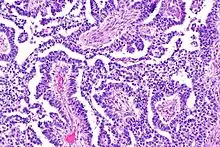

The ovarian yolk sac tumors, also known as endodermal sinus tumors, are accountable for approximately 15.5% of all OGCTs.[11] They have been observed in women particularly in their early ages, and rarely after 40 years of age.[12] The critical pathologic features are a smooth external surface and capsular tears due to their rapid rate of growth. A study consisting of 71 individual cases of ovarian yolk sac tumor provides evidence to the proliferation of the tumor. In one of the cases, the pelvic examination revealed normal activity until a 9 cm and 12 cm sized tumor was discovered 4 weeks later.[12] In another case, a 23 cm tumor was discovered in a pregnant woman who was monitored regularly and had normal findings until oophorectomy became essential.[12] Histologically, these tumors are characterized by mixed solid and cystic components.[1] The mixed solid components are characterized by a soft gray to yellow solid components accompanied with significant hemorrhage and necrosis. The cysts are approximately 2 cm in diameter and populated throughout the tissue which results in giving the neoplasm a ‘honeycombed appearance’.[1]